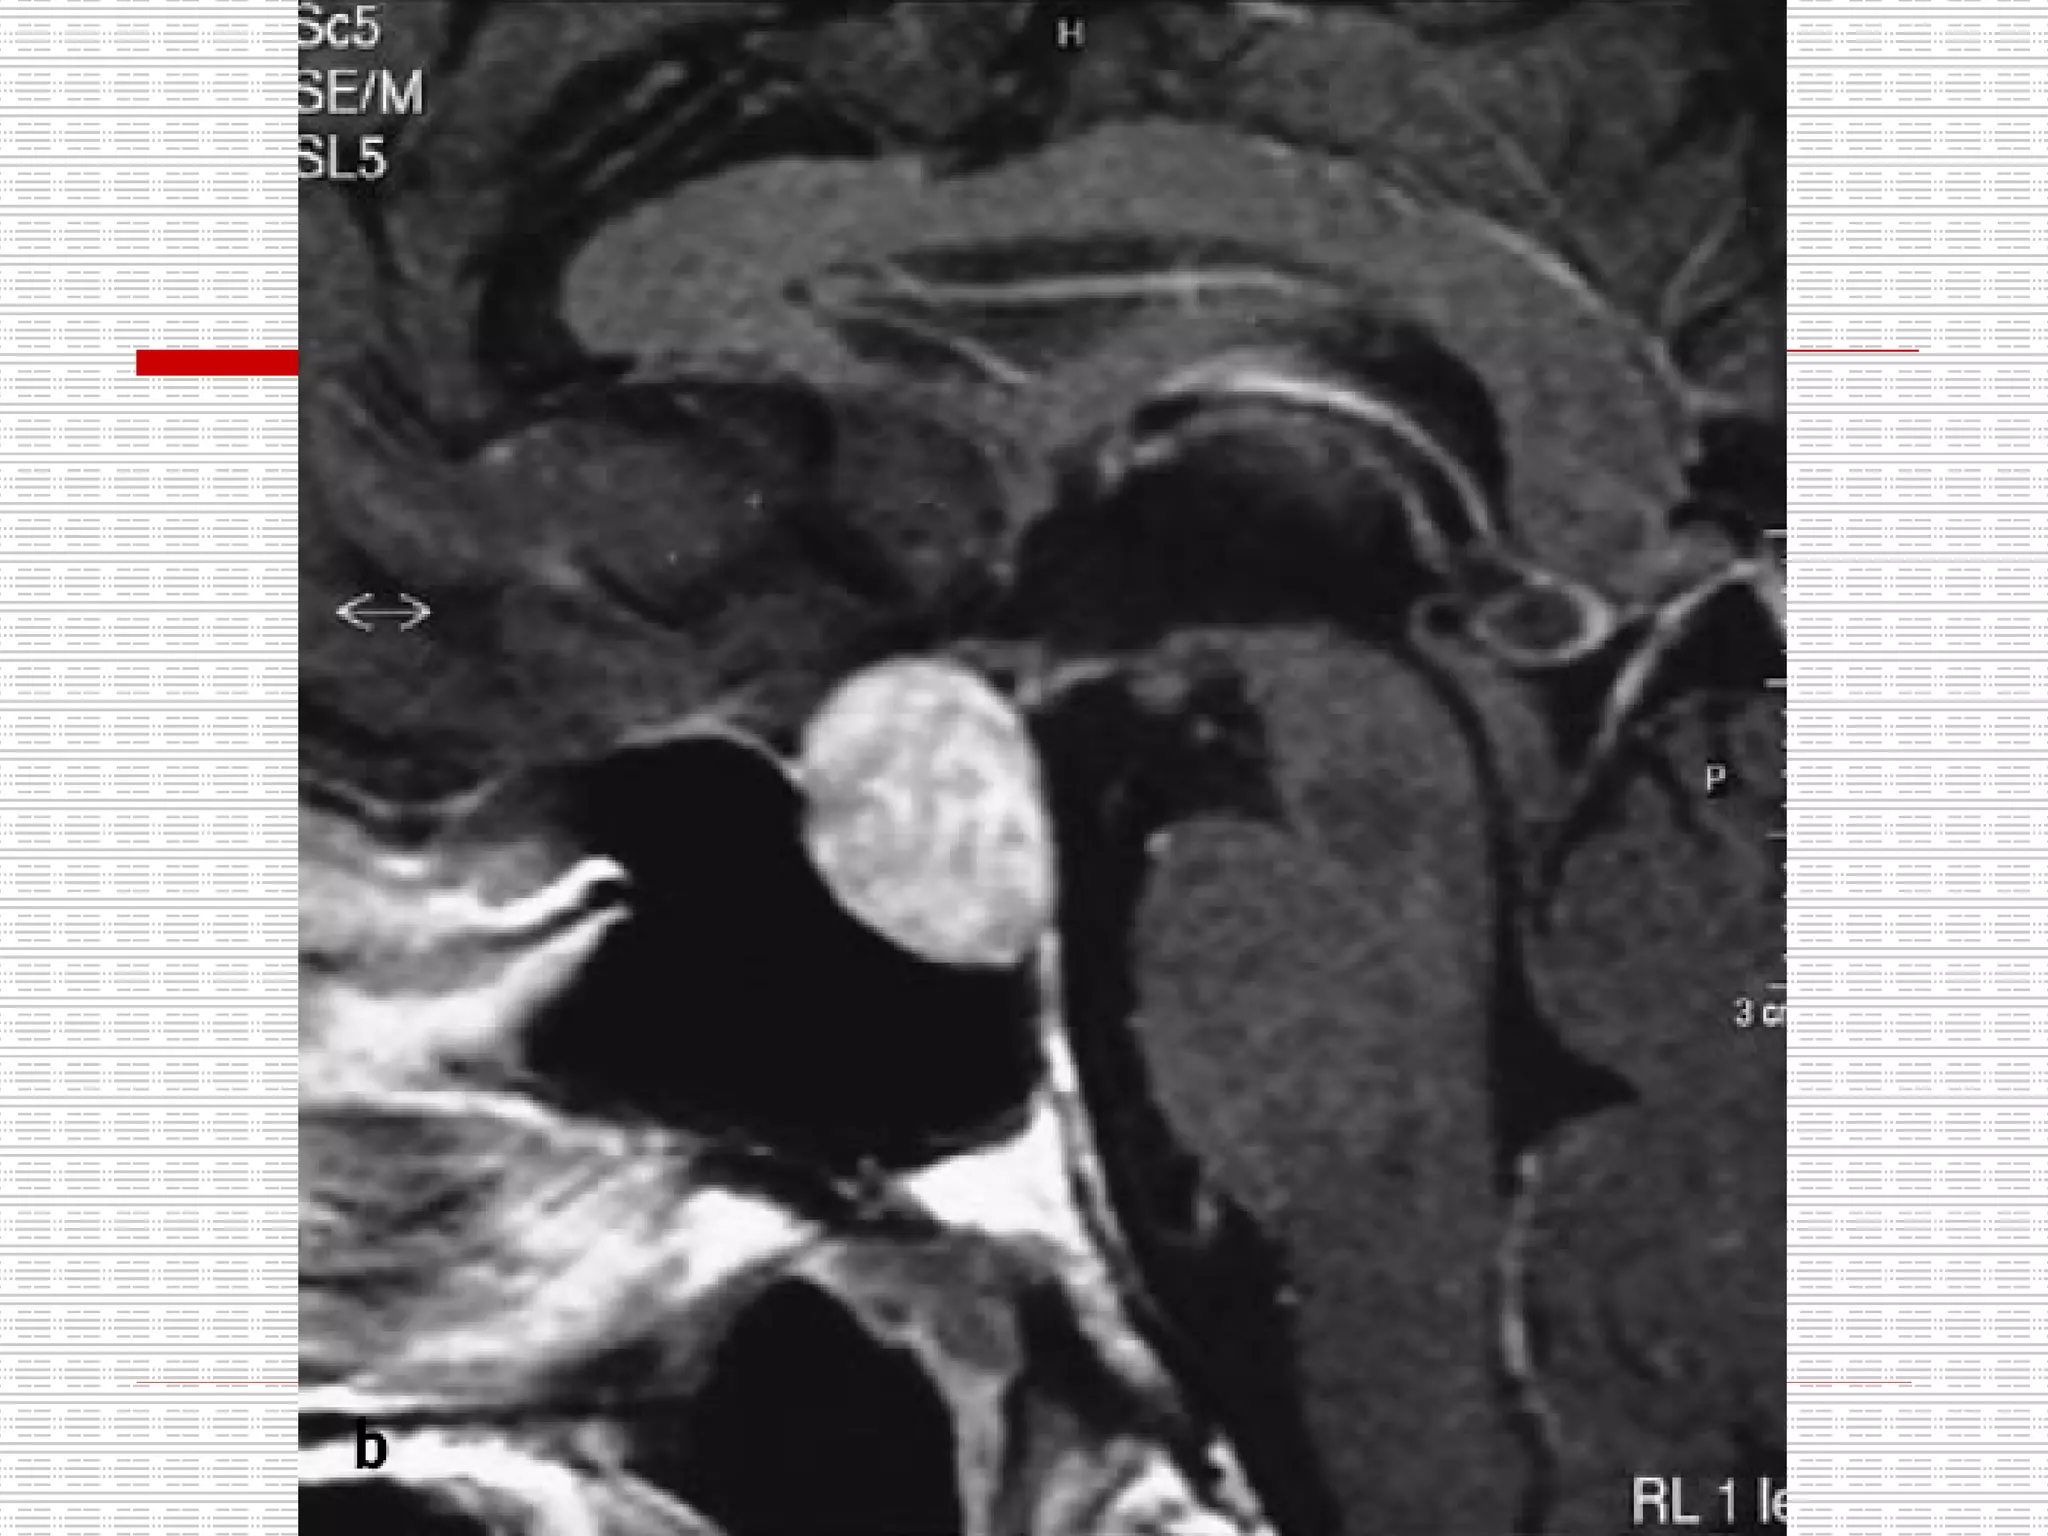

CT: Enlarged pituitary fossa with bony scalloping and soft tissue opacification

CT: Enlarged pituitaryfossa with bony scalloping and soft tissue opacification